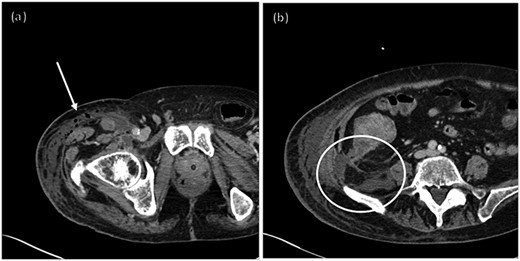

An 84-year old man presented to the Emergency Department from his nursing home acutely febrile and encephalopathic with melanotic stool. His pertinent past medical history included stroke with residual left hemiparesis and gastrointestinal bleed one year prior. He was not anticoagulated and had no surgical history or prior colonoscopy (Table 1). On initial evaluation his heart rate was 92, blood pressure 95/51, and he was obtunded. His laboratory values (Table 2) demonstrated acute anemia, acute renal failure, and concern for infectious process with procalcitonin of 14 ng/mL. His stool was grossly heme-positive. Physical examination revealed dry mucous membranes, a non-tender and non-distended abdomen, and no evidence of skin changes nor infection. He was volume resuscitated, initiated on broad spectrum antibiotics, and admitted to the intensive care unit (ICU) with presumed diagnoses of gastrointestinal bleed and sepsis of unknown etiology given an elevated lactic acid and procalcitonin with hypotension. Gastroenterology was consulted at the time of admission for endoscopy given his history of melanotic stool and anemia. Endoscopy was deferred after improvement with resuscitation and no continued evidence of active bleeding. After initial resuscitation his laboratory values and hemodynamics normalized and he returned to baseline mental status. He did not elicit history of weight loss, decreased appetite, recurrent melanotic stool, or alterations in bowel habits in the past year. Within 24 hours of ICU admission he developed right hip erythema, induration, and pain. On examination, there was no crepitus. CT of the right hip (Fig. 1) demonstrated concern for necrotizing soft tissue infection with gas involving the right retroperitoneum and upper thigh without evidence of abscess. General surgery was consulted for necrotizing fasciitis but due to the patient’s poor functional status and need for highly morbid surgery, operative intervention was declined by the patient’s durable power of attorney. He unexpectedly clinically improved with non-operative treatment over the following 32 hours, prompting evaluation for alternative etiologies of his soft tissue infection. CT of his abdomen and pelvis (Fig. 2) demonstrated a 7.1 cm proximal right colon mass with invasion into the retroperitoneum and gas tracking into adjacent soft tissues concerning for a perforated malignancy. A CT abdomen and pelvis were not obtained prior to this due to lack of abdominal symptoms, non-tender examination, and family decision for non-operative management. Colorectal surgery was consulted and although tumor resection with debridement would obtain source control, the widespread soft tissue infection would still require extensive debridement. After goals of care discussions, the patient and his family elected for palliative care. He was subsequently transitioned to hospice care and expired 10 days later.